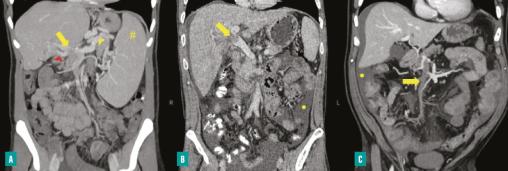

Images scanographiques de patients présentant une thrombose de la veine porte (coupe coronale, phase portale).

A. Cavernome porte sur thrombose de la veine porte (TVP) sans hépatopathie sous-jacente (#  : splénomégalie  ; flèche jaune  : thrombose porte  ; pointe jaune  : varices porto-cave  ; pointe rouge  : cavernome).

B. Thrombose de la veine porte sur foie de cirrhose (flèche jaune  : thrombose porte  ; point jaune  : ascite).

C. Thrombose de la veine porte avec extension à la veine mésentérique supérieure compliquée d’ischémie mésentérique (flèche jaune  : thrombose de la veine mésentérique supérieure  ; point jaune  : ascite).